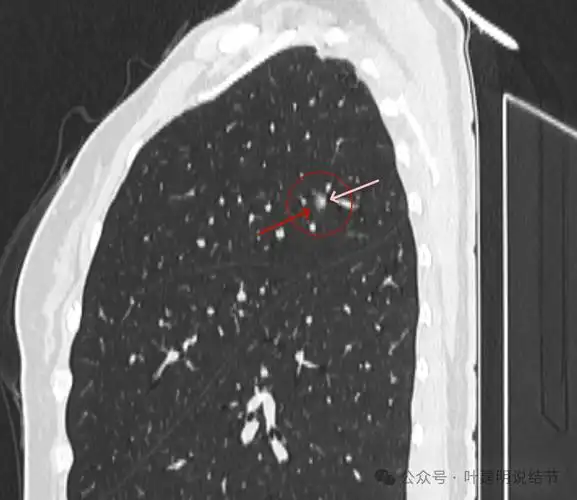

问诊分析:肺混合磨玻璃结节就得尽快手术?其实也可多年不进展的!